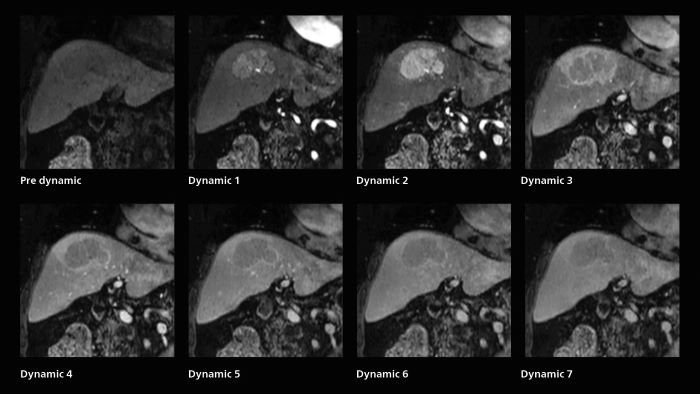

For patients with acute cerebral infarction, who cannot endure long examinations, some clear benefits of SmartSpeed emerge. “We have a fast MR scan protocol that quickly completes the scanning. It allows us to acquire all the images we need in about 3 to 5 minutes,” says Dr. Katahira. “And it is often possible to acquire more images at that level, which is an advantage because the exam is complete even if the patient moves in the middle of the exam.” Also in dynamic MRI of the liver Dr. Katahira sees important improvements. While previously his scan used 9 seconds for a 5 mm slice, SmartSpeed now allows him to achieve a thin slice volume scan (1.6 x 2.1 x 2mm) with double arterial phase using acceleration factor 8. He indicates this is very useful for the radiologist when diagnosing, especially because it can provide a high temporal resolution.

A patient was referred for MR imaging of HCC. A double arterial volume dynamic study was performed. Since it is a volume dynamic study, it can also be evaluated using MPR images. Performed on Elition X.

The hospital’s routine ExamCard for dynamic MRI of the liver uses total scan duration 1:05 min, dynamic scan time 9.2 sec, 1.6 x 1.8 x 2.0 mm, 200 slices, acceleration factor 8.